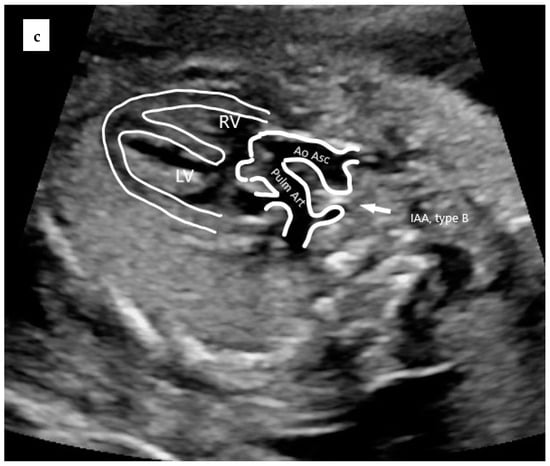

Figure 2 illustrates an example of a prenatal case with TAC. Parental counseling by pediatric cardiologists and geneticists was part of the prenatal work-up. Karyotyping including fluorescent in situ hybridization for 22q11.2 microdeletion was offered. The data were collected from medical files, as well as from stored ultrasound images and video loops, whenever they were available.

Figure 2.

Prenatal echocardiography of TAC. (a) The five-chamber view showing the presence of a thickened truncal valve that overrides a large VSD (arrow); (b) The three vessels view showing two vessels: superior vena cava and truncal vessel (subtype A1): pulmonary trunk arising from the truncal vessel); (c) example of subtype A4 in which aorta and MPA arise from the common arterial trunk and interrupted aorta divides into brachiocephalic and left common carotid arteries (IAA Type B). TV = truncal vessel; VSD = ventricular septal defect; LV = left ventricle; RV = right ventricle; PT = pulmonary artery trunk, Ao Asc = ascending aorta; Pulm Art = pulmonary artery; IAA = interrupted aortic arch.